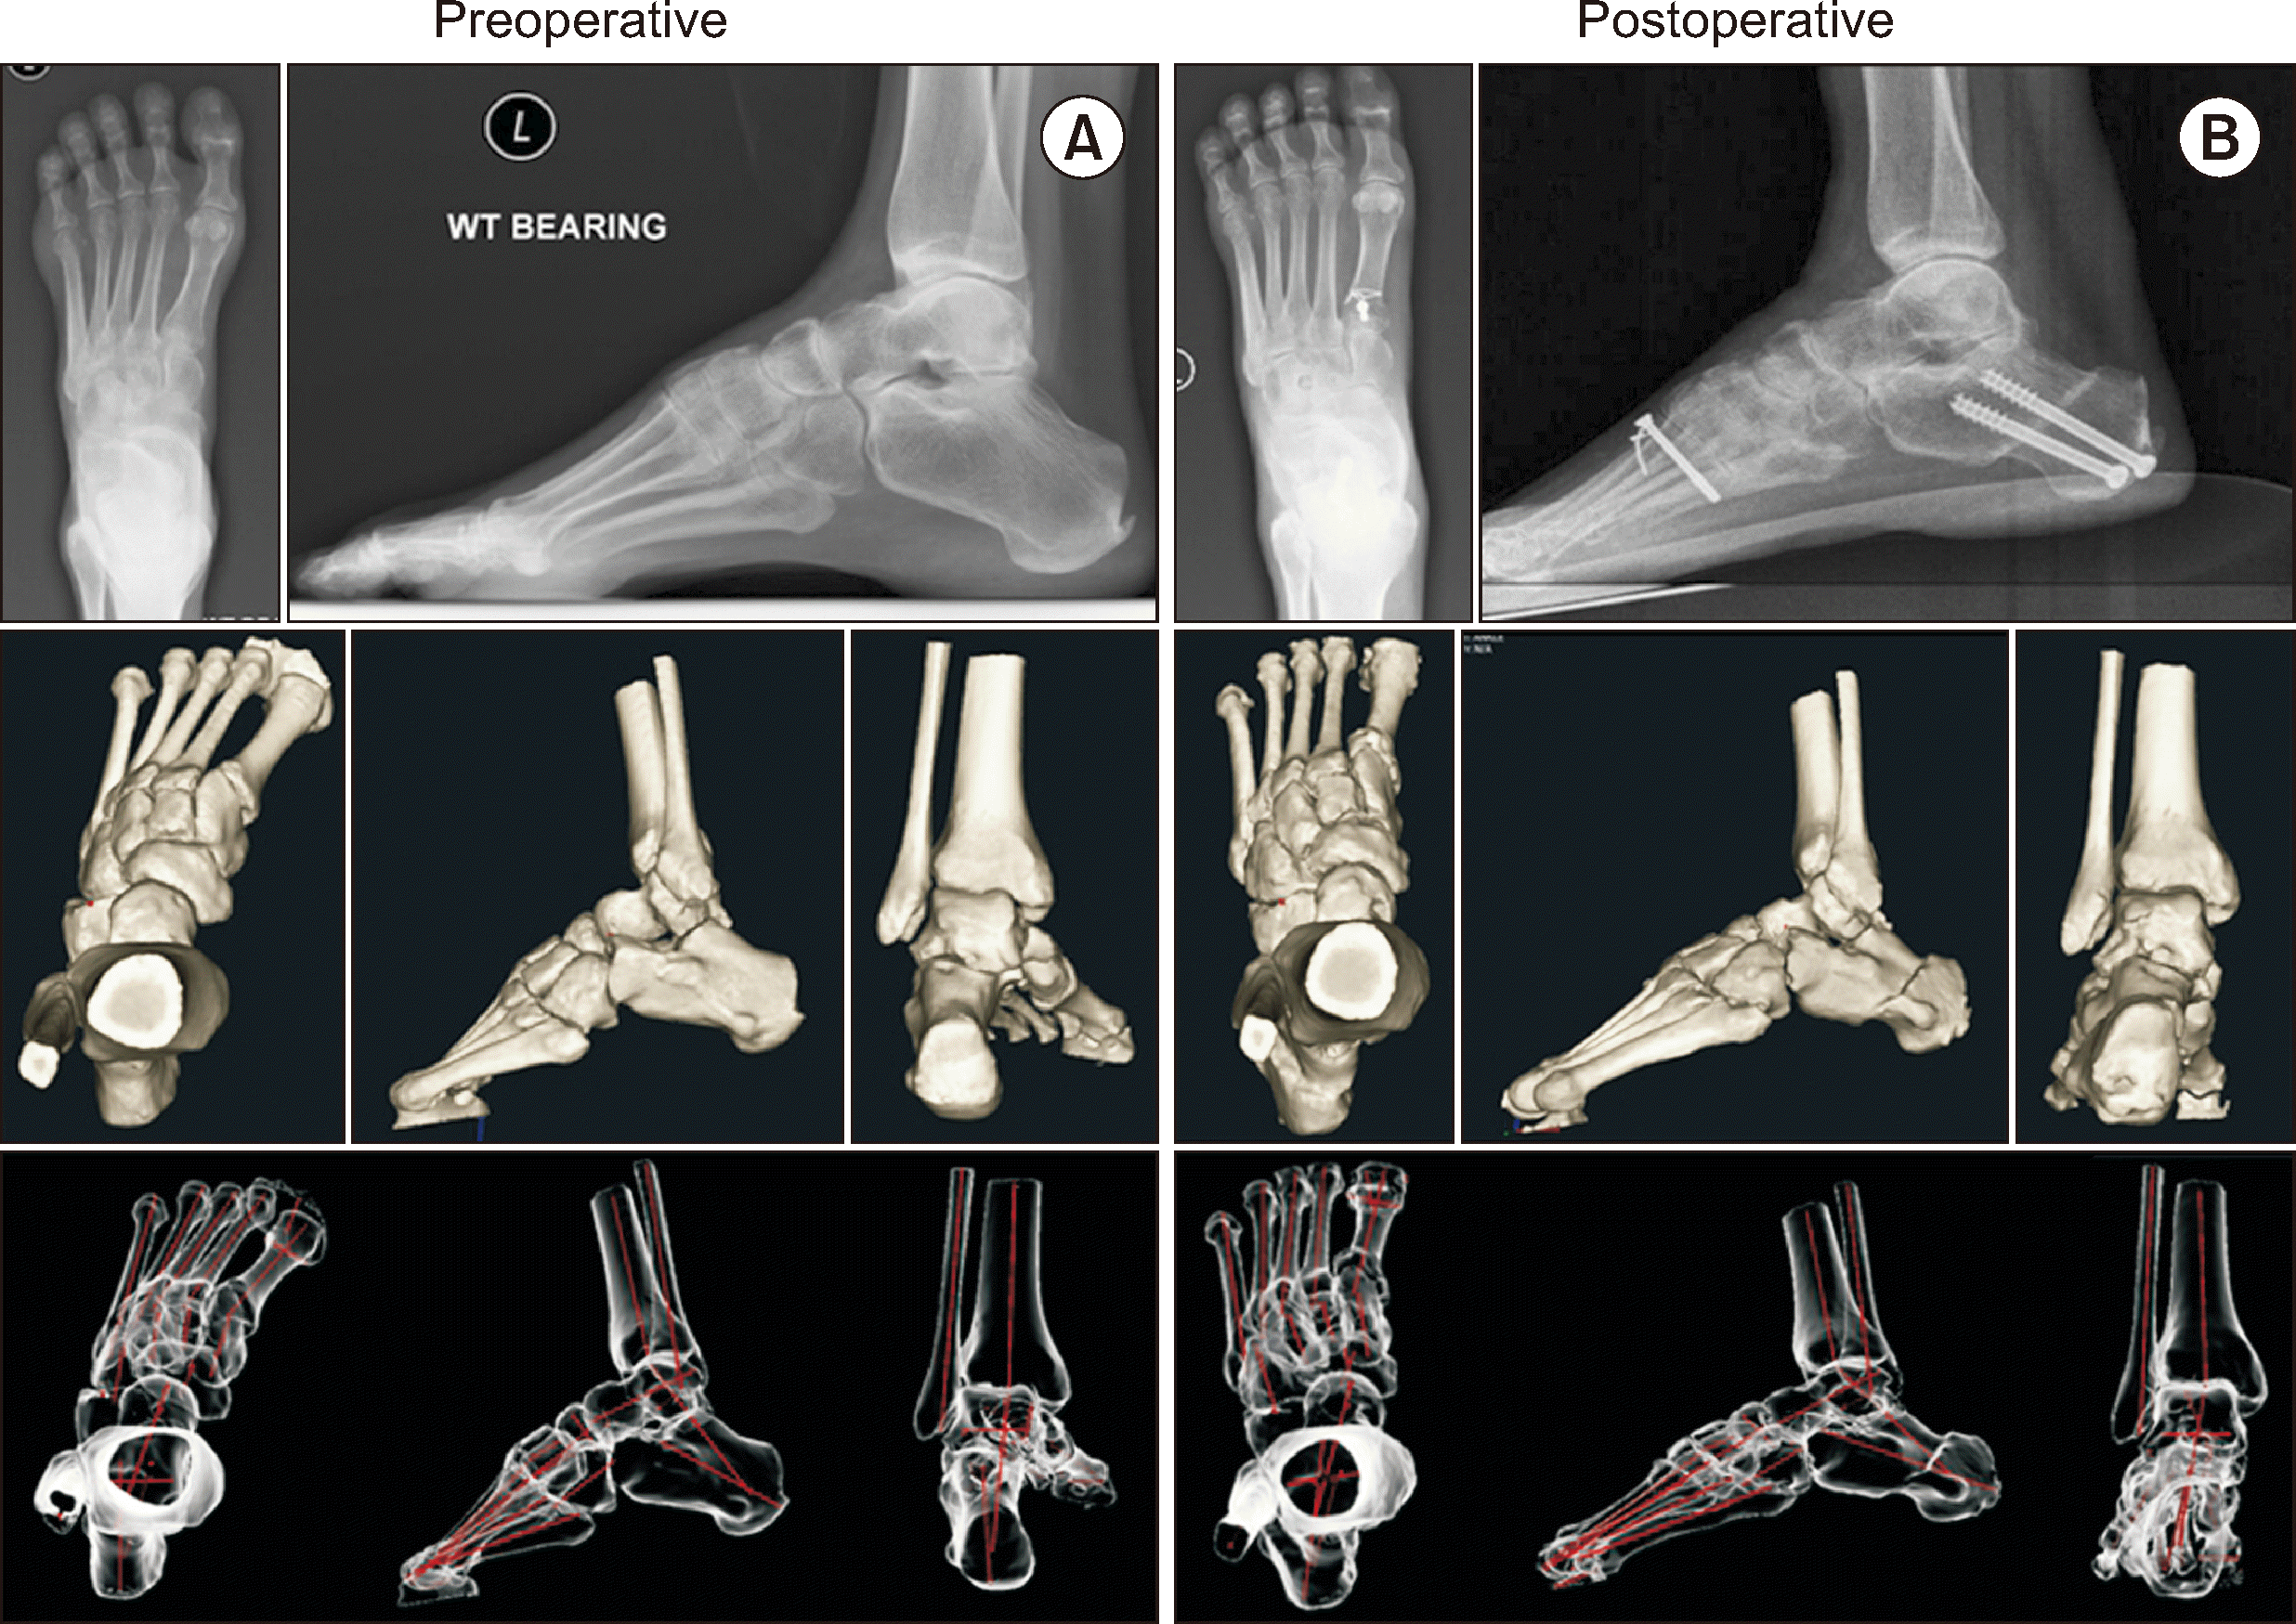

Song 등11)은 29명의 CMT 환자를 대상으로 진행한 관절 보존 술식의 효과를 수술 전후 족부의 WBCT 이미지를 자동화 분석 소프트웨어를 이용하여 분석하였고 연구 결과 관절 보존 술식이 CMT 족부의 시상면, 축상면, 관상면의 변형을 효과적으로 교정하였음을 보고하였다(Fig. 5). 또한 CMT 족부 변형의 교정에서 거주상 관절(talonavicular joint)의 연부 조직 유리술을 통한 관절의 정복이 가장 중요한 요소임을 보고하였다. 해당 연구에서 각 수술 사례에서 진행된 평균 술식의 개수는 7.8개(5∼10개)였고 각 술식은 환자 사례에 따라 선택적으로 시행되었다. 흔히 시행된 수술로는 수술 순서에 따라 경피적 아킬레스건 연장술(Achilles triple hemisection, 79.3%), 후경골건 유리술(82.8%), 거주상 관절 및 스프링 인대 유리술(89.7%), 경피적 장족지굴곡건 절단술(62.1%), 중족부 족저근막 유리술(93.1%), 장비골건 유리술(93.1%), 종골 절골술(82.8%), 장비골건의 단비골건 이전술(93.1%), 제 1중족골의 배측 폐쇄형 쐐기 절골술(86.2%) 및 후경골건 이전술(82.8%) 등이 있었다(Table 2).11) 그 외 시행된 술식으로는 신전건의 중족부 이전술(장무지신전건 및 장족지신전건을 각각 내측 및 외측 설상골로 이전), 장족지굴곡건 및 장무지굴곡건 이전술, 비복근 연장술 및 외측 발목 인대 봉합술 등이 포함되었다. 1차 수술 후 재수술이 필요하였던 사례는 후족부 정렬의 과교정으로 인해 재수술을 진행하였던 한 사례가 있었다.

외번력을 강화하기 위하여 이전할 수 있는 힘줄이 존재하지 않거나 절골술 및 힘줄 이전술 등으로도 교정되지 않는 심한 변형의 관절, 통증을 동반하는 관절염 병변이 있는 경우에는 거골하 관절 유합술 또는 삼중 유합술이 권고된다(Fig. 8).1) 이러한 유합술은 유합술 단독이 아닌 필요 시 연부조직 유리술, 절골술, 힘줄 이전술을 동시에 진행하는 것이 권고된다.3) 유합술은 가급적 최후에 고려되어야 할 술식이며 특히 나이가 젊은 환자일수록 관절 보존 술식을 우선적으로 고려해야 한다.

Figure 5

Preoperative and postoperative radiographic results of the left foot of a 52-year-old female CMT patient who underwent joint sparing surgery. (A) Preoperative and (B) postoperative standing foot radiographs, weight-bearing 3D computed tomography images, and 3D model with segmental bone axes (red lines) generated by the software. CMT: Charcot–Marie–Tooth, WT: weight.

Figure 8

Preoperative and postoperative radiographic results of the left foot of a 40-year-old female CMT patient who underwent joint fusion surgery. (A) Preoperative and (B) postoperaive standing foot radiographs and weight-bearing 3D computed tomography images. CMT: Charcot–Marie–Tooth.